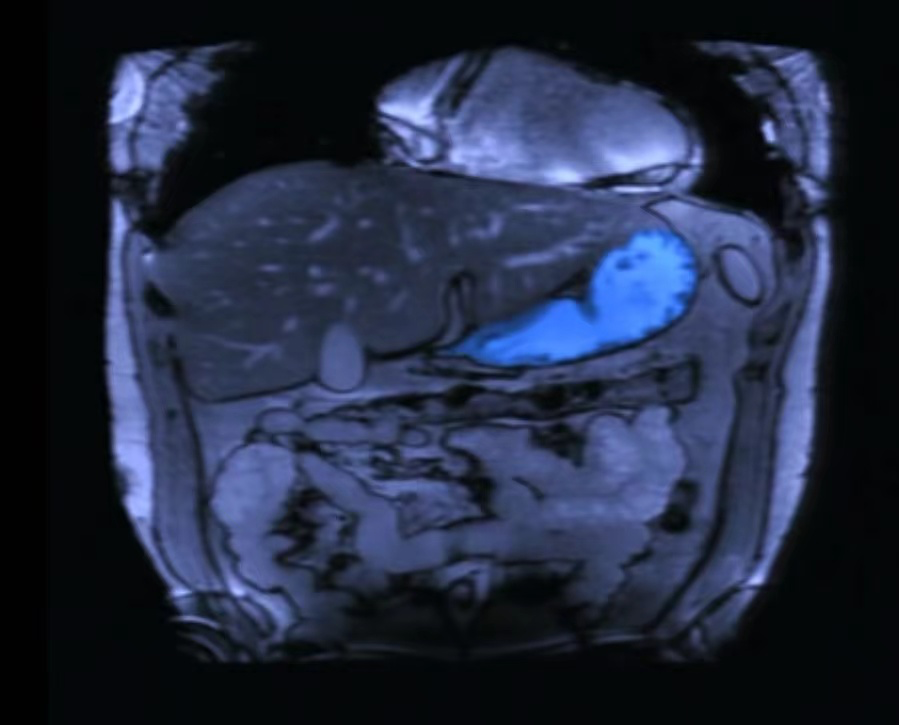

长期高盐饮食,尤其是配合了幽门螺杆菌感染,原本红润饱满的胃黏膜逐渐变薄发生萎缩,功能也慢慢被影响。

更大的危害有可能随之出现:胃有可能会从萎缩继续进展到早期胃癌。

这时候的图片看起来还好,的确,如果在此时发现胃癌,还是有很大希望治愈的。

但如果再晚一点儿,发展成进展期胃癌即便积极治疗,也有大半的生命无法挽救。

中国是胃癌大国,幽门螺杆菌、高盐腌制饮食,是已知的重要危险因素。检查治疗幽门螺杆菌,养成多吃新鲜、少腌制、低盐的饮食习惯,是我们能做到的。

同时也不要忽略了胃镜检查筛查胃癌,及时发现胃癌端倪预防治疗处理。